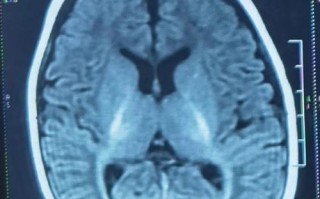

缺氧缺血性脑病 的MRI表现

HIE的MRI表现与损伤发生时的胎龄密切相关。

• 足月儿/近足月儿

• 皮层层状坏死:最典型的表现,在T1像上,大脑皮层(尤其是顶枕叶)出现沿脑回分布的高信号带(代表神经元坏死、出血和吞噬细胞浸润);在T2像上则呈低信号

• 基底节和丘脑损伤:这些区域对缺氧极度敏感,在T1像上呈对称性高信号,在T2像上呈对称性低信号,这种“双侧基底节丘脑病变”是足月儿HIE的特征性表现。

• 脑水肿:脑沟变浅,脑室受压变窄。

• 后期改变:数周后,坏死区域会形成软化灶(T1低信号,T2高信号),并可能导致脑萎缩